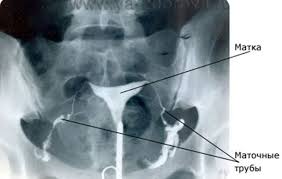

Проверка проходимости труб (ГСГ) - гистеросальпингография.

Гистеросальпингографию можно делать с использованием рентгеновской установки и ультразвукового аппарата. В первом случае это рентгеновская ГСГ (Rg-ГСГ), во втором - ультразвуковая (сонографическая, эхографическая) ГСГ (УЗ-ГСГ).

Проводится ГСГ преимущественно до овуляции, дабы исключить влияние рентегна на оплодотворенную ЯЦ. Но врачи советуют вообще в этом цикле предохранятся!!!ПРОЦЕДУРА ГСГ ПРОВОДИТСЯ ТОЛЬКО ПРИ "ЧИСТОМ" МАЗКЕ!!!!

Расшифровка ГСГ http://www.babyblog.ru/community/post/conception/1475719